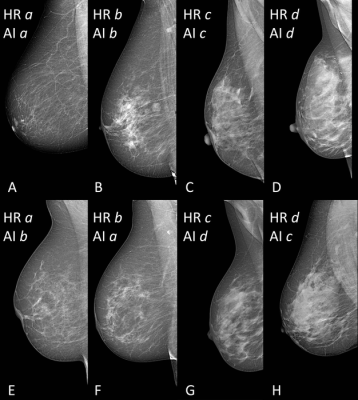

In clinical practice, breast density is visually assessed on two-view mammograms, most commonly with the American College of Radiology Breast Imaging-Reporting and Data System (BI-RADS) four-category scale, ranging from Category A for almost entirely fatty breasts to Category D for extremely dense. The system has limitations, as visual classification is prone to inter-observer variability, or the differences in assessments between two or more people, and intra-observer variability, or the differences that appear in repeated assessments by the same person.

To overcome this variability, researchers in Italy developed software for breast density classification based on a sophisticated type of AI called deep learning with convolutional neural networks, a sophisticated type of AI that is capable of discerning subtle patterns in images beyond the capabilities of the human eye. The researchers trained the software, known as TRACE4BDensity, under the supervision of seven experienced radiologists who independently visually assessed 760 mammographic images.

TRACE4BDensity showed 89% accuracy in distinguishing between low density (BI-RADS categories A and B) and high density (BI-RADS categories C and D) breast tissue, with an agreement of 90% between the tool and the three readers. All disagreements were in adjacent BI-RADS categories.